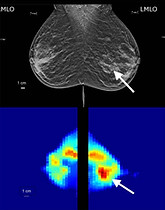

Healthy participant and tumor detection figures adapted from Mojabi P, Tsang RY, Docktor B, et al. Feasibility of tumor detection with a transmission-based microwave imaging system. Med Phys. 2025; 52:e18080. https://doi.org/10.1002/mp.18080 © 2025 The Author(s). https://creativecommons.org/licenses/by/4.0/. Figures displayed in orientation familiar to radiologists.